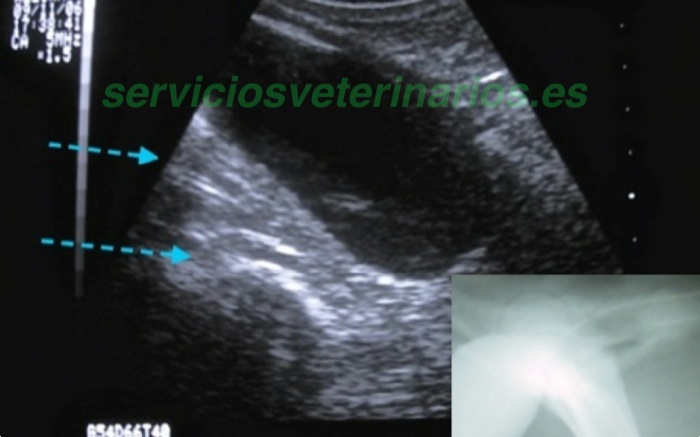

En la ecografía se ve entre colon y vejiga dos sondas que han sido introducidas por los meatos accesorios laterales aunque es necesaria la confirmación que se hace al mover desde el exterior las sondas. En la radiografía la introducción de contraste en vejiga por el meato central de vagina marca bien la silueta de la vejiga y pone de manifiesto un segundo drenaje al exterior del contraste.